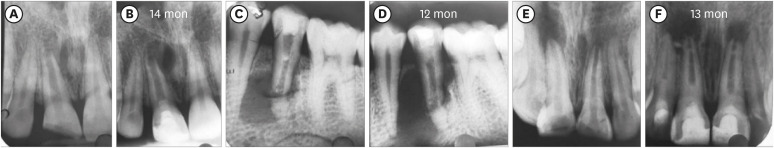

Figure 2 shows representative cases of each group BC, PRP, and PRF.

Figure 2

Intraoral periapical radiograph evaluation. (A, B) Blood clot group: No. 1: bone healing (BH)-3, apical closure (AC)-3, root wall thickness (RWT)-3, root length (RL)-1. (C, D) Platelet-rich plasma group: No. 1 (tooth #21): BH-3, AC-3, RWT-3, RL-3, No. 2 (tooth #22: mature): BH-3. Platelet-rich fibrin group: No. 1 (tooth #11): BH-3, AC-3, RWT-3, RL-2, No. 2 (tooth #12: mature): BH-3. Arrow indicates intracanal calcification.

1. BH

Two teeth in the BC group (No. 11 and 12) did not show any sign of BH, and 3 teeth in the PRP group (No. 8, 11, and 12: Figure 3) showed an increased size of the lesion radiographically (Table 1) and were scored 0. In contrast, in the PRF group, all the 11 teeth showed evidence of BH, having a score of excellent (3) in 4, good (2) in 5, and fair (1) in 2 teeth. Among the 3 groups, excellent (3) scores were most often found (n = 6) in the BC group (50%), while 3 teeth exhibited a good (2) score, and 1 tooth had a fair (1) score. In the PRP group, the number of teeth having excellent (3) BH was 3, while a good (2) score was found in 4 teeth, and a fair (1) score in 2 teeth. Considering the number of teeth with good and excellent scores in the 3 groups, it appeared that better BH took place in the teeth of the BC group, followed by the PRF and then the PRP groups, although no significant difference was observed (p = 0.62) (Table 3).

2. AC

Incidentally, the number of immature teeth was 6 in each group. The BC and PRF groups had the maximum number of teeth with excellent (3) scores (4; 66.67% each) in regard to AC, whereas the remaining 2 teeth had fair (1) scores in the former group and good (2) scores in the latter group. In the PRP group, excellent (3) and good (2) scores of AC were seen in 2 teeth each, and in the remaining 2 teeth, no sign (0) of AC was observed. Based on these results, more evidence of AC was seen in the PRF group than in the BC and PRP groups, but no significant difference (p = 0.10) was identified (Table 3).

3. RWT

The BC group had the maximum number (4; 66.67%) of teeth with an excellent (3) score for RWT. One tooth each scored fair (1) and good (2) in this group, whereas 2 teeth in each of the PRP and PRF groups exhibited an excellent (3) score and 50% of teeth in the latter group showed a good (2) score for RWT, while the remaining tooth had a fair (1) score. However, in the former group, 2 teeth showed no sign (0) of RWT, with scores of fair (1) and good (2) for the remaining 2 teeth. Therefore, RWT was evidenced more in the BC group, followed in descending order by the PRF and PRP groups, although there were no significant differences among them (p = 0.63) (Table 3).

4. RL

Fifty percent of the immature teeth in BC and PRF group showed a fair (1) score. Two teeth exhibited a good (2) score in both groups, and the remaining 1 tooth showed no sign (0) of RL in each group. Excellent (3) RL was seen in 1 tooth in the PRP group only. In another tooth, the score was good (2) and in the remaining 4 teeth, it was equally distributed between fair (1) and no sign (0). Considering the distribution of good and excellent scores among the 3 groups, it appears that better RL was seen in the PRP group, followed by BC and PRF groups, but with no significant difference among them (p = 0.79) (Table 3).